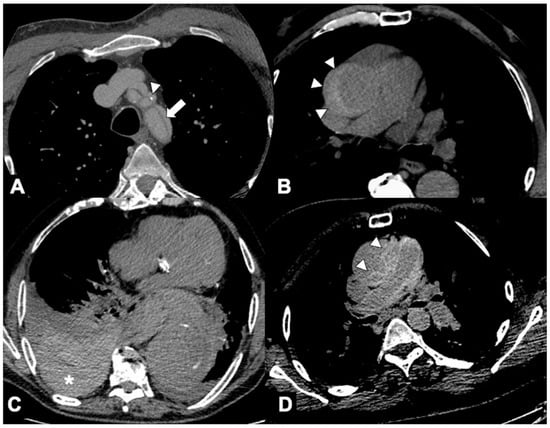

- A low-dose, non-gated, non-contrast phase, with coverage from the lung apex to the lower abdomen, which is useful to evaluate the presence of aortic intramural hematoma, displaced intimal calcification, surgical material, and high-density pericardial, pleural, or mediastinal blood (Figure 2). The radiation dose of the non-contrast phase should be kept low by using wider collimation and low tube potential with concomitant reduction in the tube current. Nowadays, dual-source technology provides a virtual non-contrast phase obviating the need to acquire a non-enhanced phase.

- A non-gated delayed phase (about 70 s delay) obtained to assess for late filling of a false lumen (FL), to clearly depict abdominal organ malperfusion, contrast extravasation due to aortic rupture and to evaluate peri-adventitial enhancement indicating acute aortitis.